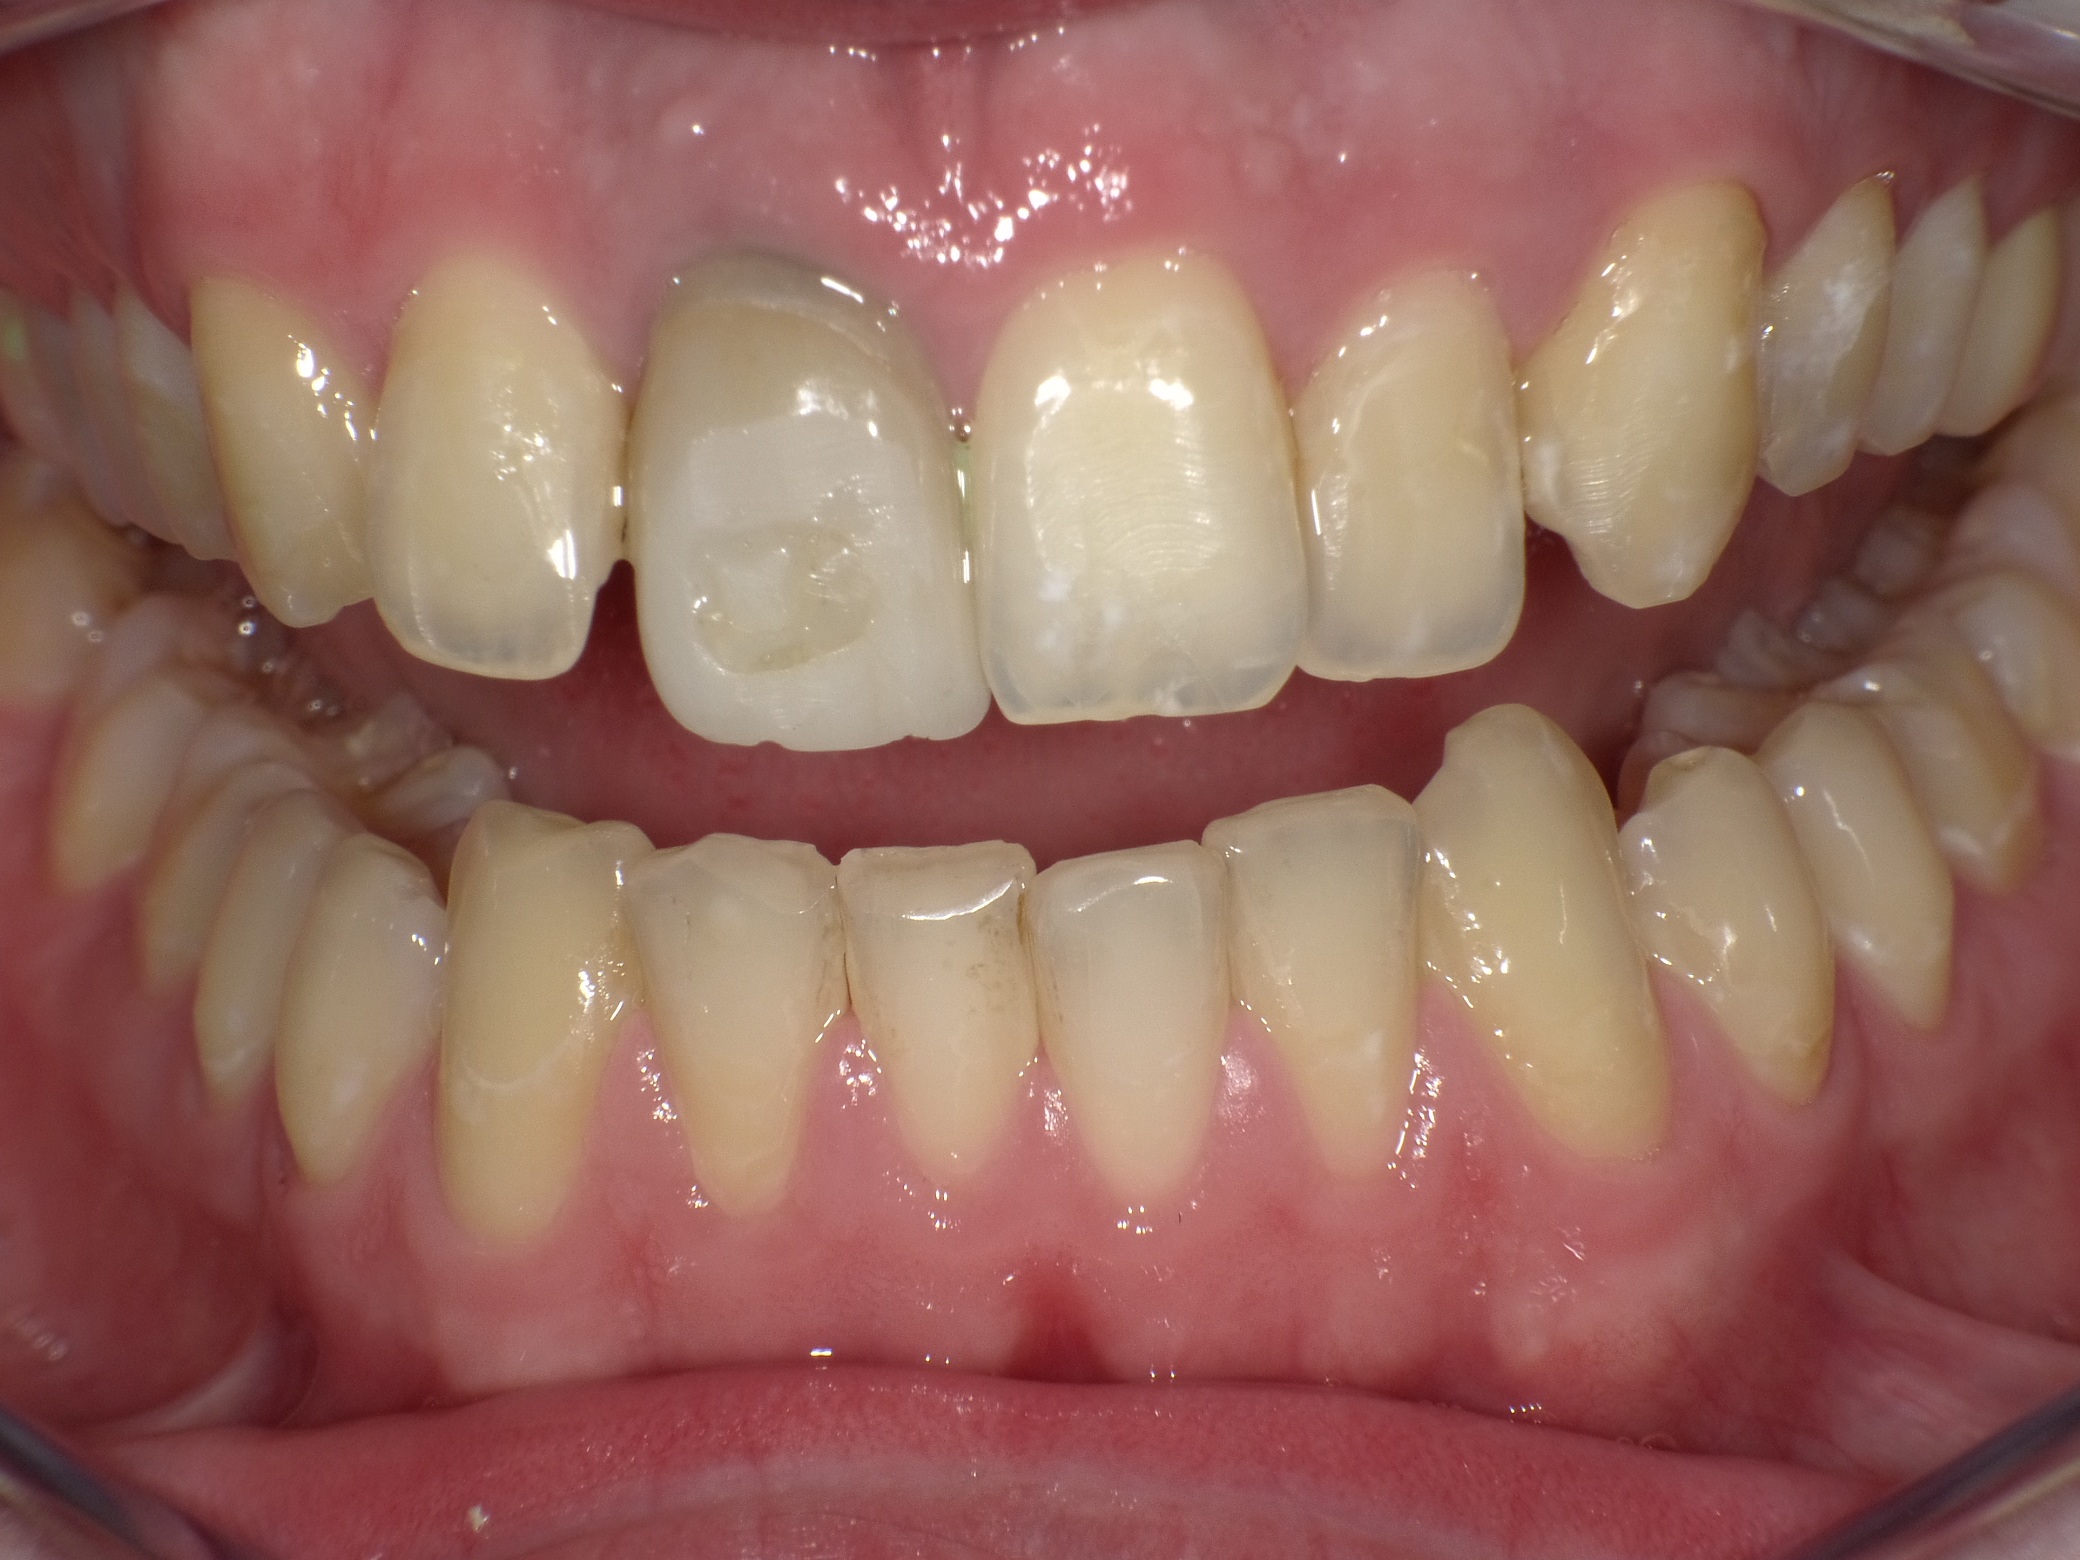

Abradierte, gelbliche Zähne mit vielen Kunststoff-Füllungen und Kronen, die der Patientin nicht gefallen haben

Vorher: Abradierte, gelbliche Zähne mit vielen Kunststoff-Füllungen und Kronen, die der Patientin nicht gefallen haben

Leuchtende Zähne durch vollkeramische Veneers und Teilkronen in nur 2 Terminen

Nachher: Leuchtende Zähne durch vollkeramische Veneers und Teilkronen in nur 2 Terminen